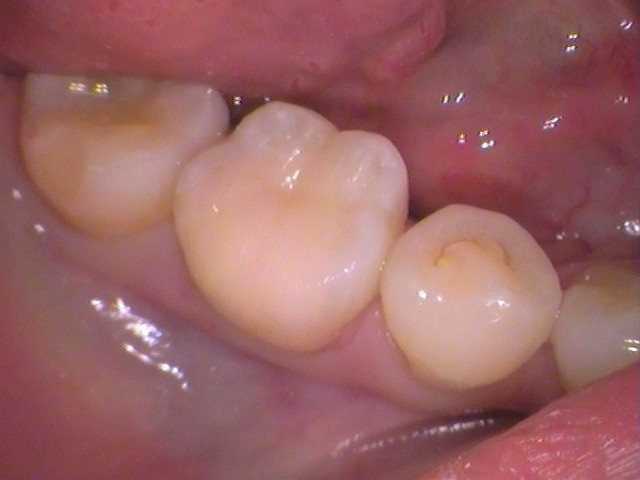

セラミックがセットされました。

歯にピッタリと入り、綺麗に仕上がりました(^-^)

症状もなくなり、日々の生活の辛さがなくなったとの事です。

無事治療が終わって良かったですね(*^-^*)